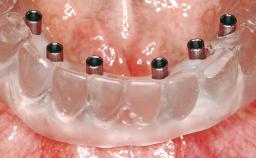

# of Implants 8

Type of Implants One-Piece

Defining Characteristics Fully edentulous upper jaw to be rehabilitated with four or more implants

Modality Fixed hybrid bridge on 5+ implants